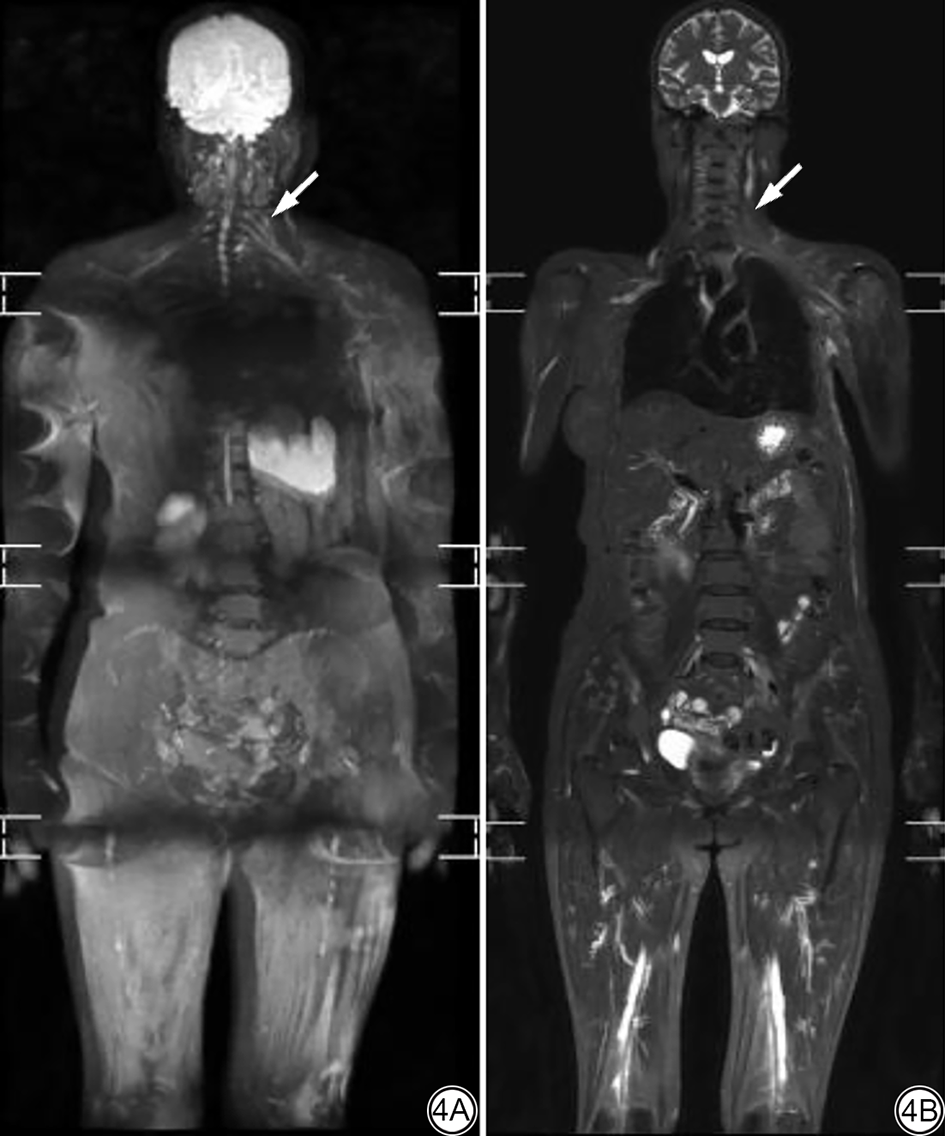

对有随访结果的116个显著病变的临床管理路径及最终结局进行归纳。极少部分病变(4/116,3.45%)因临床症状明显或影像提示恶性,最终接受了穿刺活检或手术切除:脑胶质瘤1例、脑膜瘤2例、肾透明细胞癌1例(图2)。但绝大多数(112/116,96.55%)通过常规影像学检查或随访被证实为良性或稳定性病变[如纵隔结节、肝脏海绵状血管瘤、脾脏血管瘤、胆系扩张、胰腺IPMN、肾脏错构瘤、子宫腺肌症、附件巧克力囊肿、骨岛、内生软骨瘤(图3)、臂丛神经水肿(图4)等]。

图3  女,52岁,左乳浸润性导管癌根治术后2年。3A~3C:WB-MRI图像。3A:T2WI-STIR序列显示左侧股骨卵圆形不均匀高信号影(箭);3B:DWI序列显示病灶呈高信号;3C:对应ADC图为高信号,无弥散受限,为显著偶发病变。3D:CT冠状位重建图像显示左股骨病灶内特征性“爆米花”样钙化(箭),诊断为内生软骨瘤,WB-MRI随访2年无变化。WB-MRI:全身磁共振成像;T2WI-STIR:短时反转恢复技术的T2加权成像;DWI:扩散加权成像;ADC:表观扩散系数。

Fig. 3  Female, 52-year-old, with invasive ductal carcinoma of the left breast 2 years after radical operation. 3A to 3C: WB-MRI image. 3A: T2WI-STIR sequence shows the oval heterogeneous high signal shadow of the left femur (arrow). 3B: DWI sequence shows that the lesion is hyperintense. 3C: The corresponding ADC diagram is high signal, without diffusion limitation, and it is a significant incidental lesion. 3D: CT coronal reconstruction images show the characteristic "popcorn" calcification (arrow) in the left femoral lesion, which is diagnosed as endogenous chondroma. WB-MRI follow-up shows no change for 2 years. WB-MRI: whole-body magnetic resonance imaging; T2WI-STIR: T2-weighted imaging with short-time inversion recovery technique; DWI: diffusion-weighted imaging; ADC: apparent diffusion coefficient.